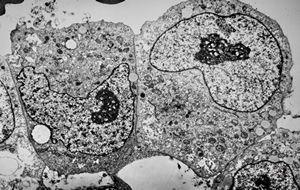

M,10y. | herpetic encephalitis